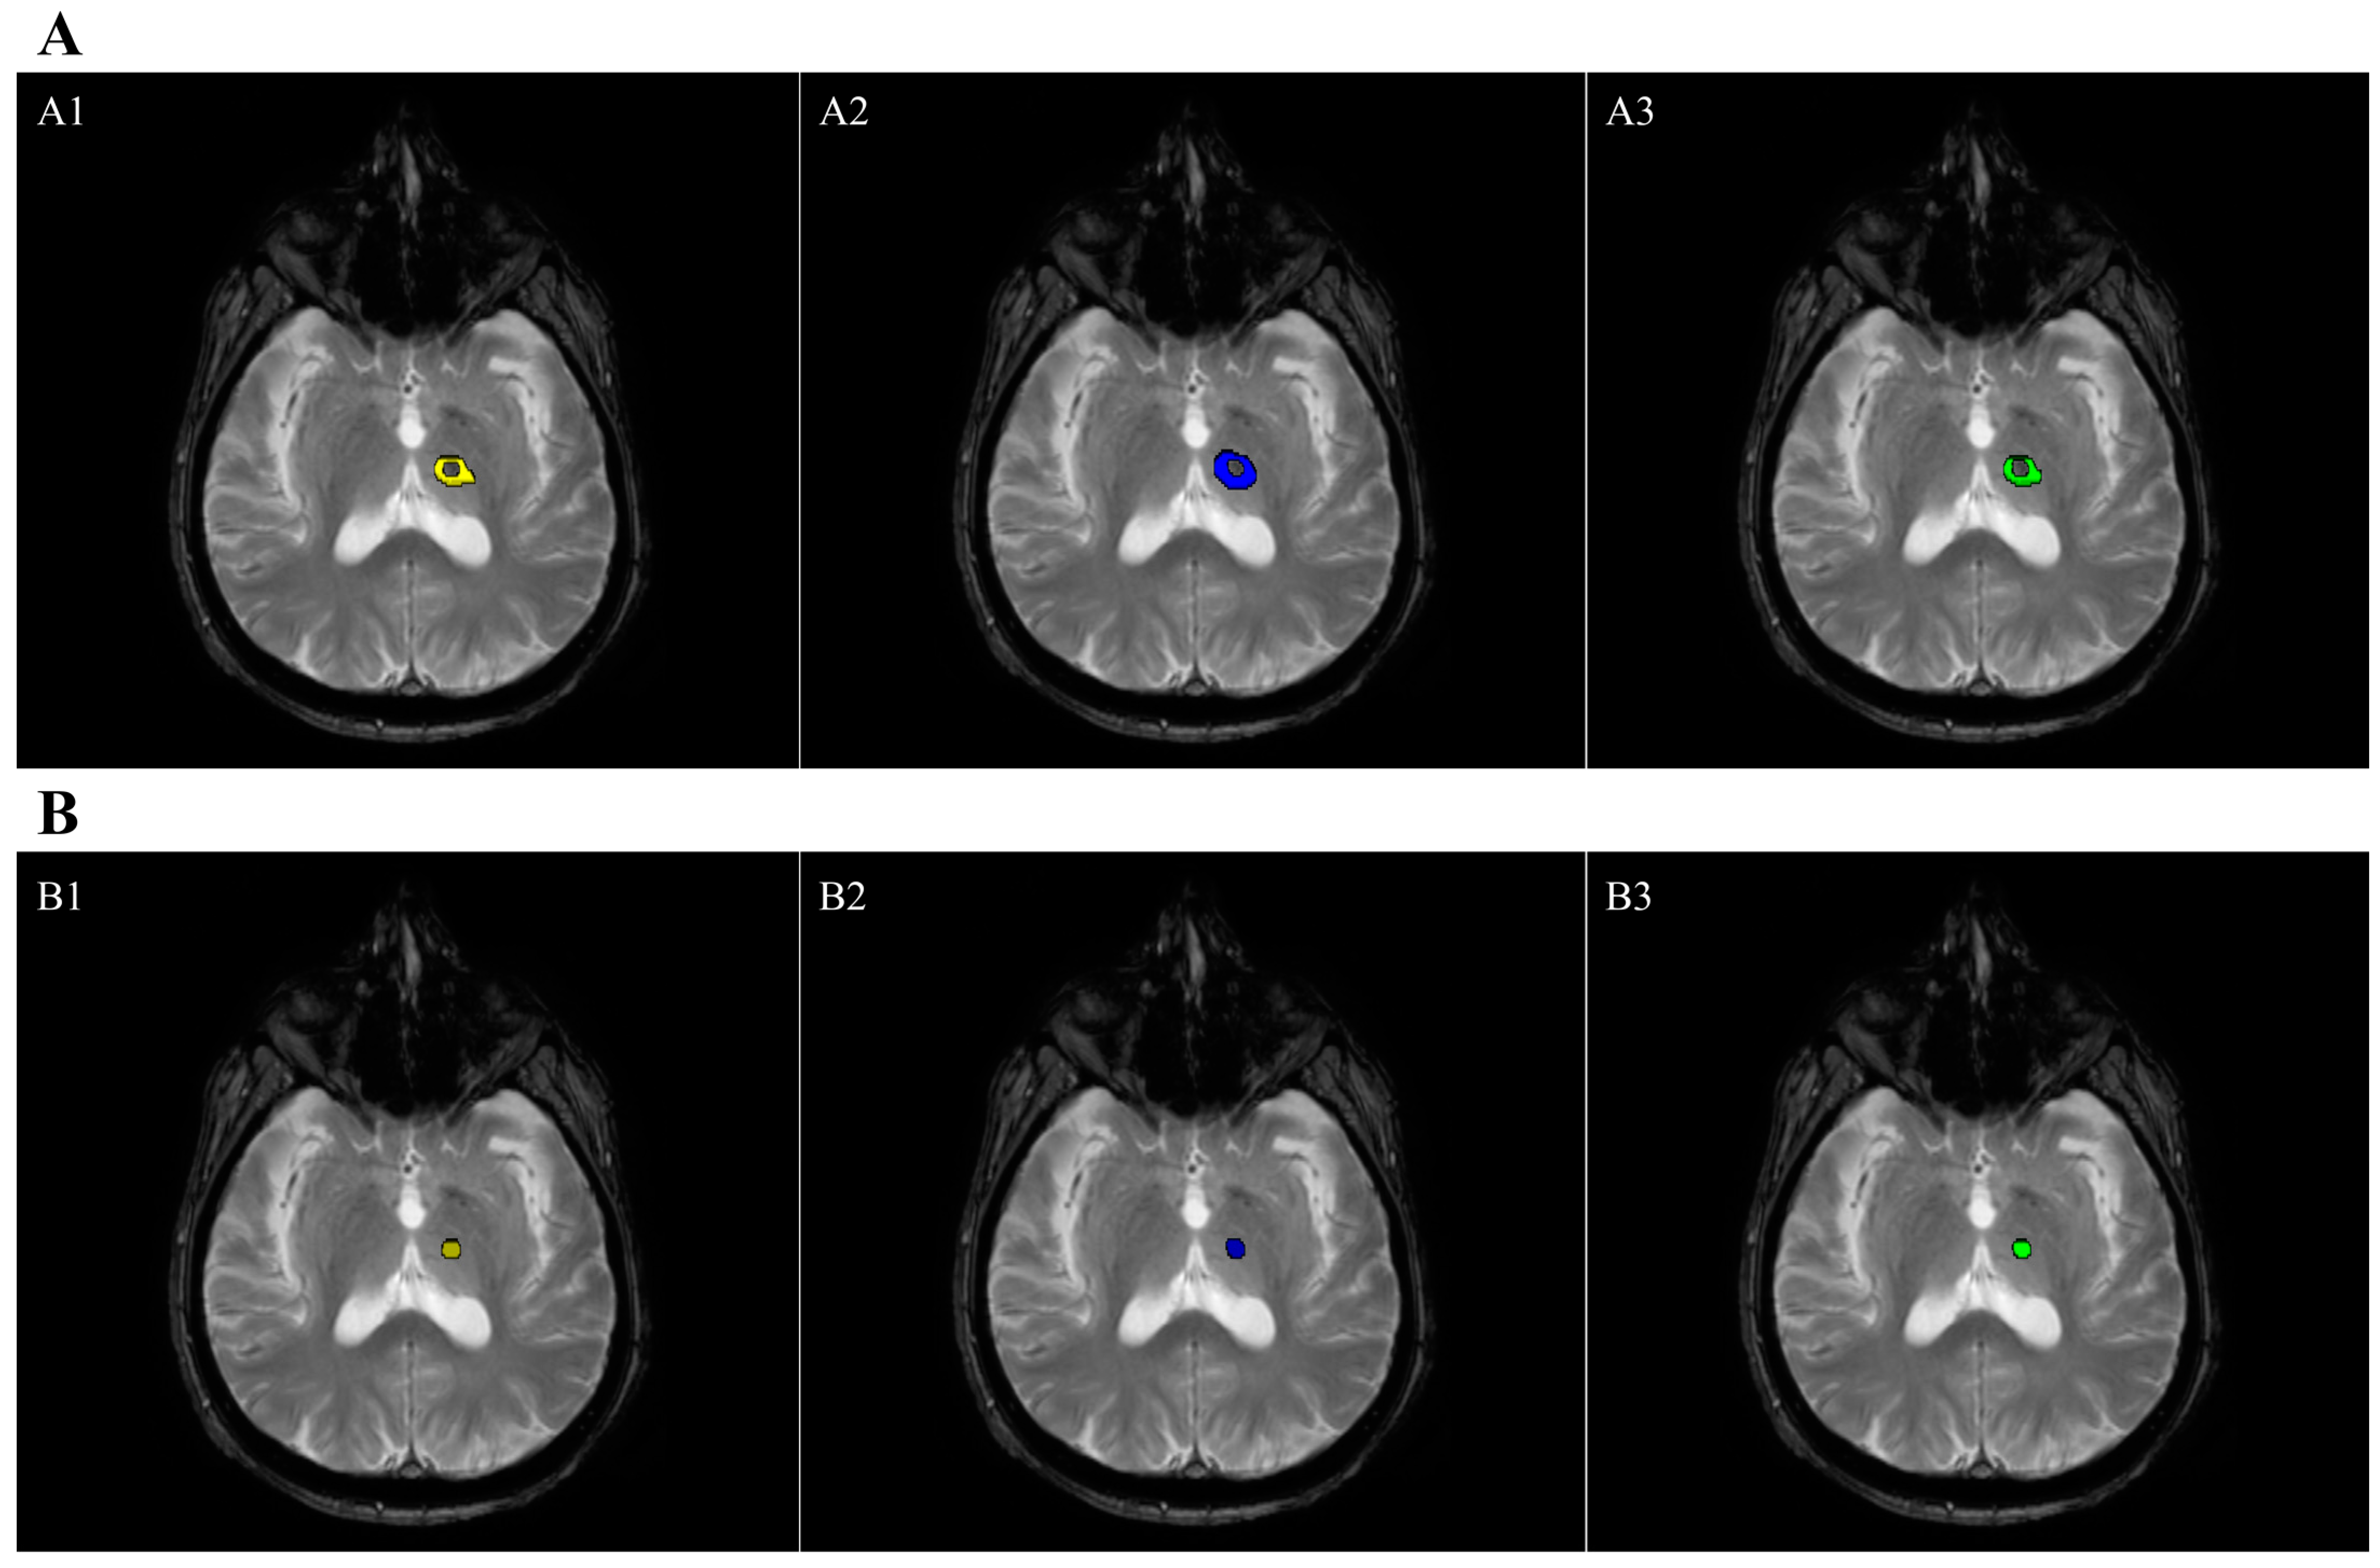

2.7. Lesion Volume Segmentation

| Edema Volume (cm3) | 1607.24 ± 705.5 | 2042.76 ± 895.92 | 0.81 | 0.74 ± 0.13 |

| Necrosis Volume (cm3) | 179.31 ± 135.72 | 153.35 ± 118.56 | 0.88 | 0.70 ± 0.11 |